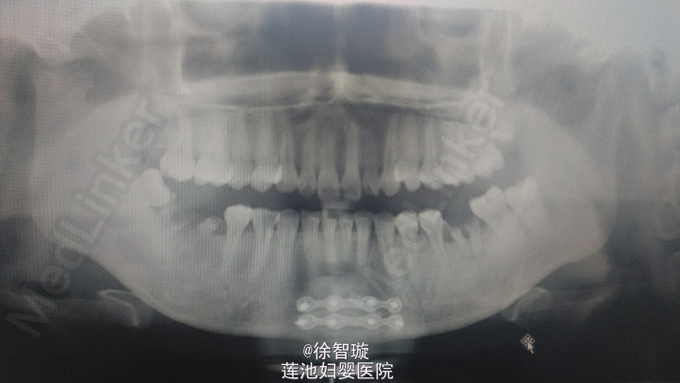

下颌骨骨折复位固定术后9个月,患者9月前因车祸致下颌骨骨折,于我院行颏部骨折切开复位内固定术,右侧髁突骨折碎片取出术,颏部磨削术,今为拆除钛板来我院就诊

颌面部基本对称,双侧关节区无压痛,右侧关节区动度弱,开口型偏右,36,46,47残根,33至43见瘢痕愈合

骨折术后钛板钛钉存留,全麻下行“下颌骨钛板钛钉取出术”